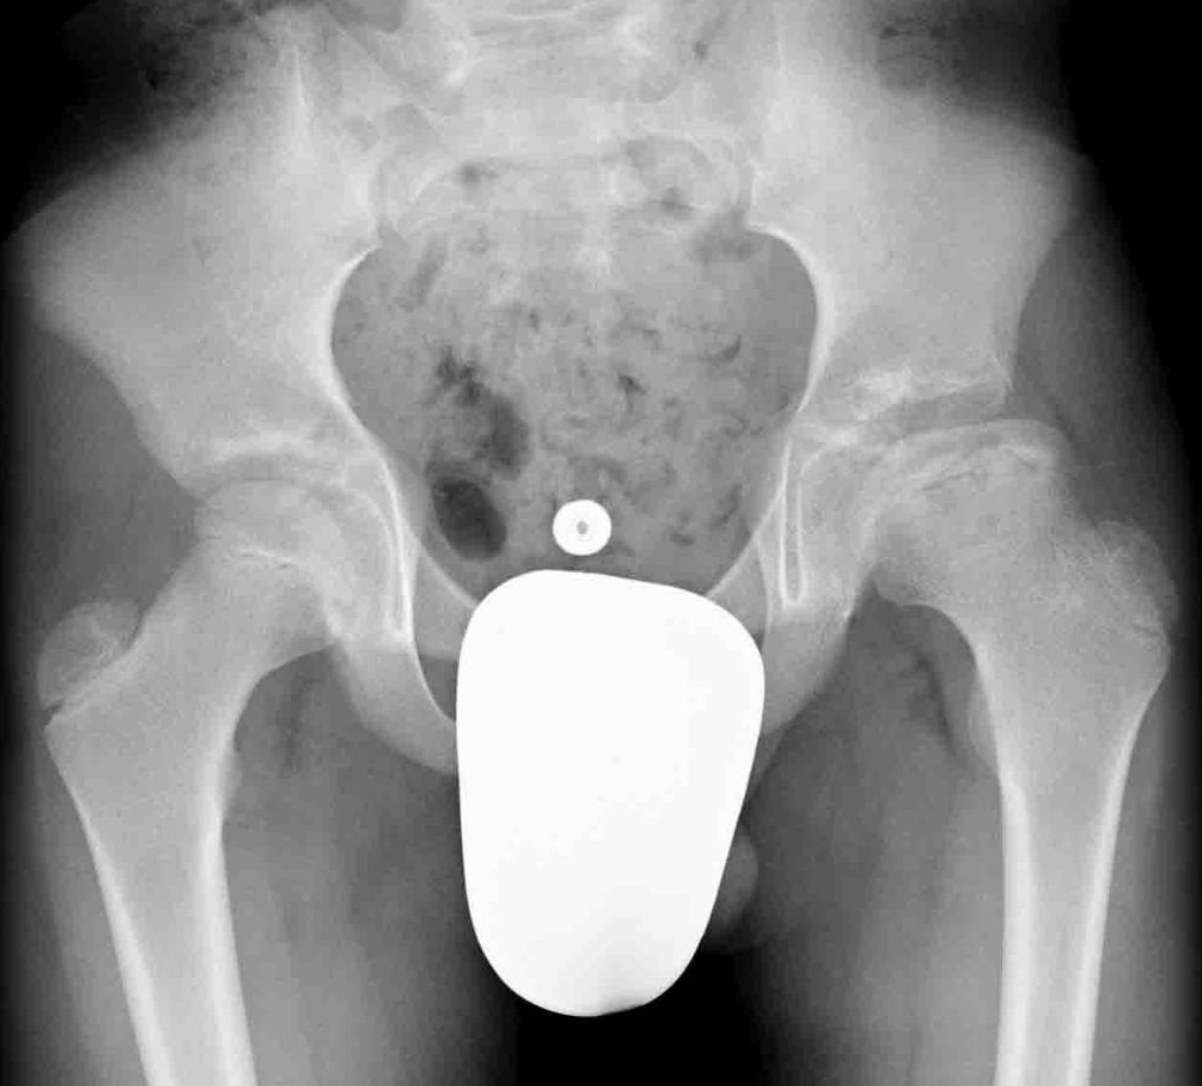

Indien er een secundaire dysplasie optreedt of abnormale beweging in het heupgewricht dan kan het zijn dat er toch een chirurgische behandeling noodzakelijk is. Soms treedt er ook overgroei van de trochanter op doordat deze meer groeit dan de heupkop. Soms is het dan ook noodzakelijk de groei van de trochanter chirurgisch te stoppen. Op volwassen leeftijd zijn soms nog bijkomende chirurgische procedures noodzakelijk als er bijvoorbeeld door de abnormale vorm van de kop een femoro-acetabulair impingment of secundaire dysplasie optreedt.